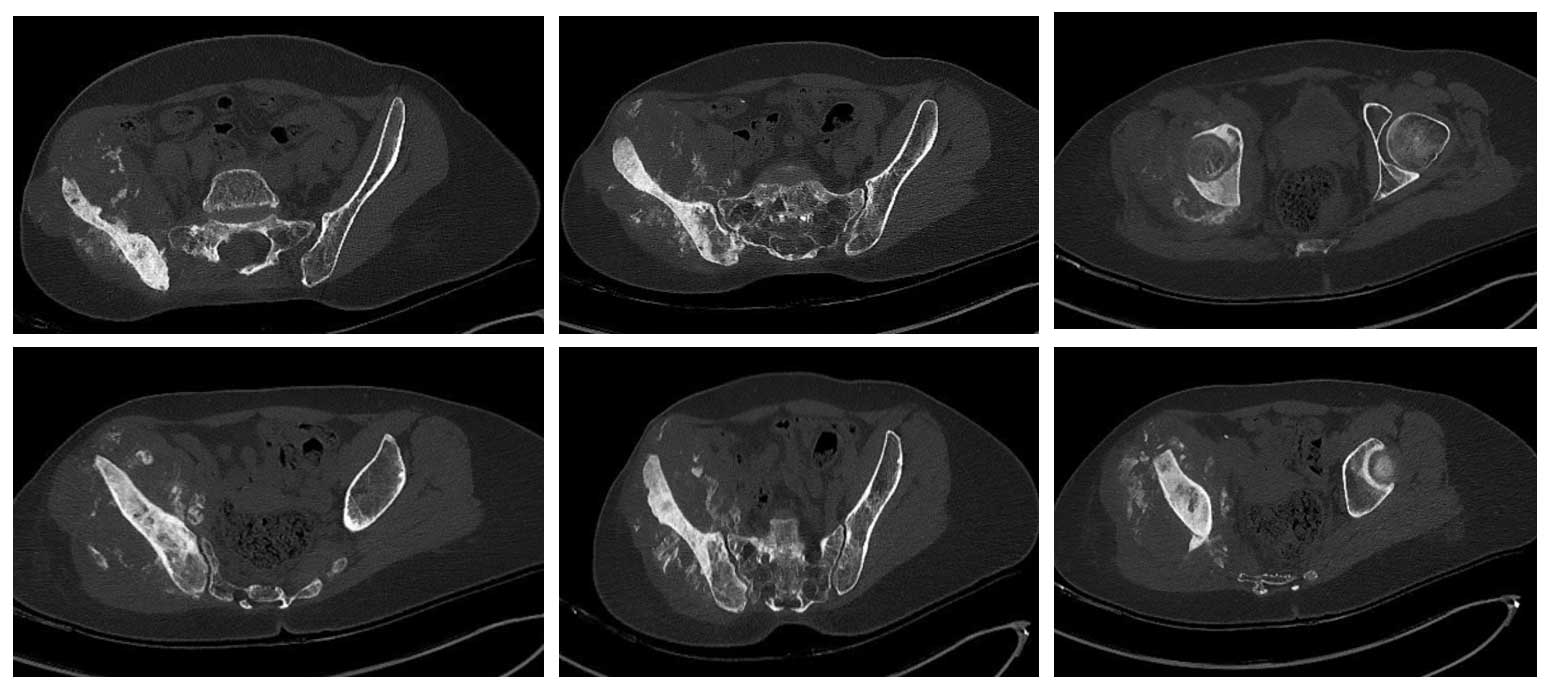

Ameliyat Öncesi: Tomografide sağ iliak kanatın tamamını içeren skleroz ve çevre yumuşak dokuda düzensiz sınırlı kitle görülmekte.